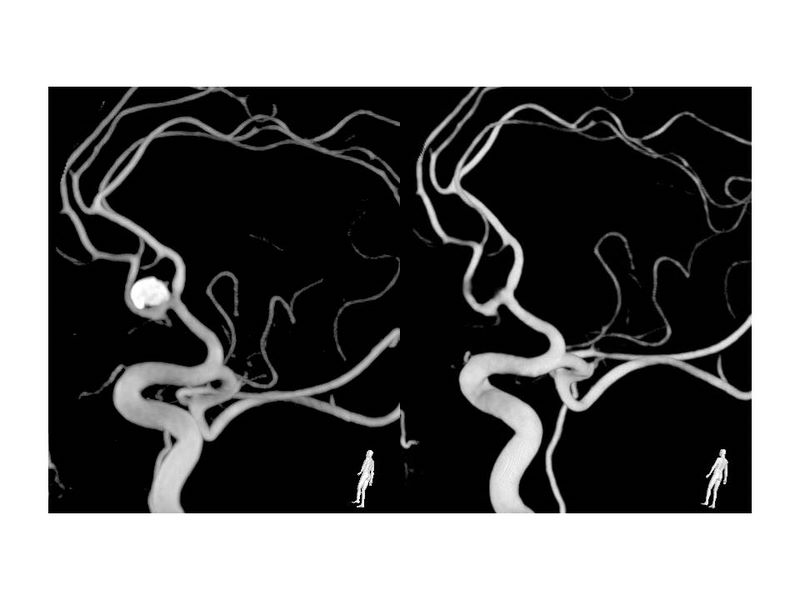

Aneurismas